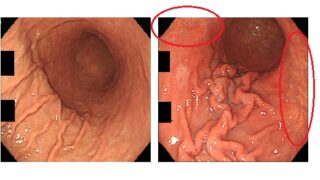

嫌儲僕、とうとう大腸カメラデビュー🎦

嫌儲野田草履、大腸がん 激痩せ&血便が止まらず間もなく金バエの元へ…